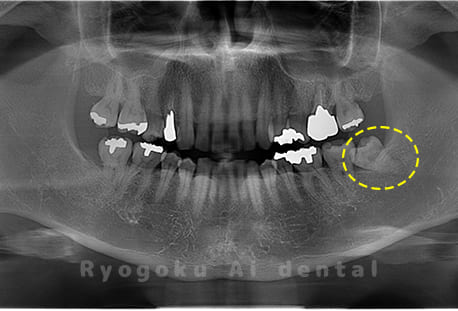

Case04

- 原因

- 上顎の親知らず、下顎の水平埋伏の親知らず

- 治療内容

- 上顎の親知らず、下顎の水平埋伏の親知らずを抜歯したケースです。

<リスク・副作用>

手術後は痛み、腫れ、痺れなどの副作用が生じる場合があります。